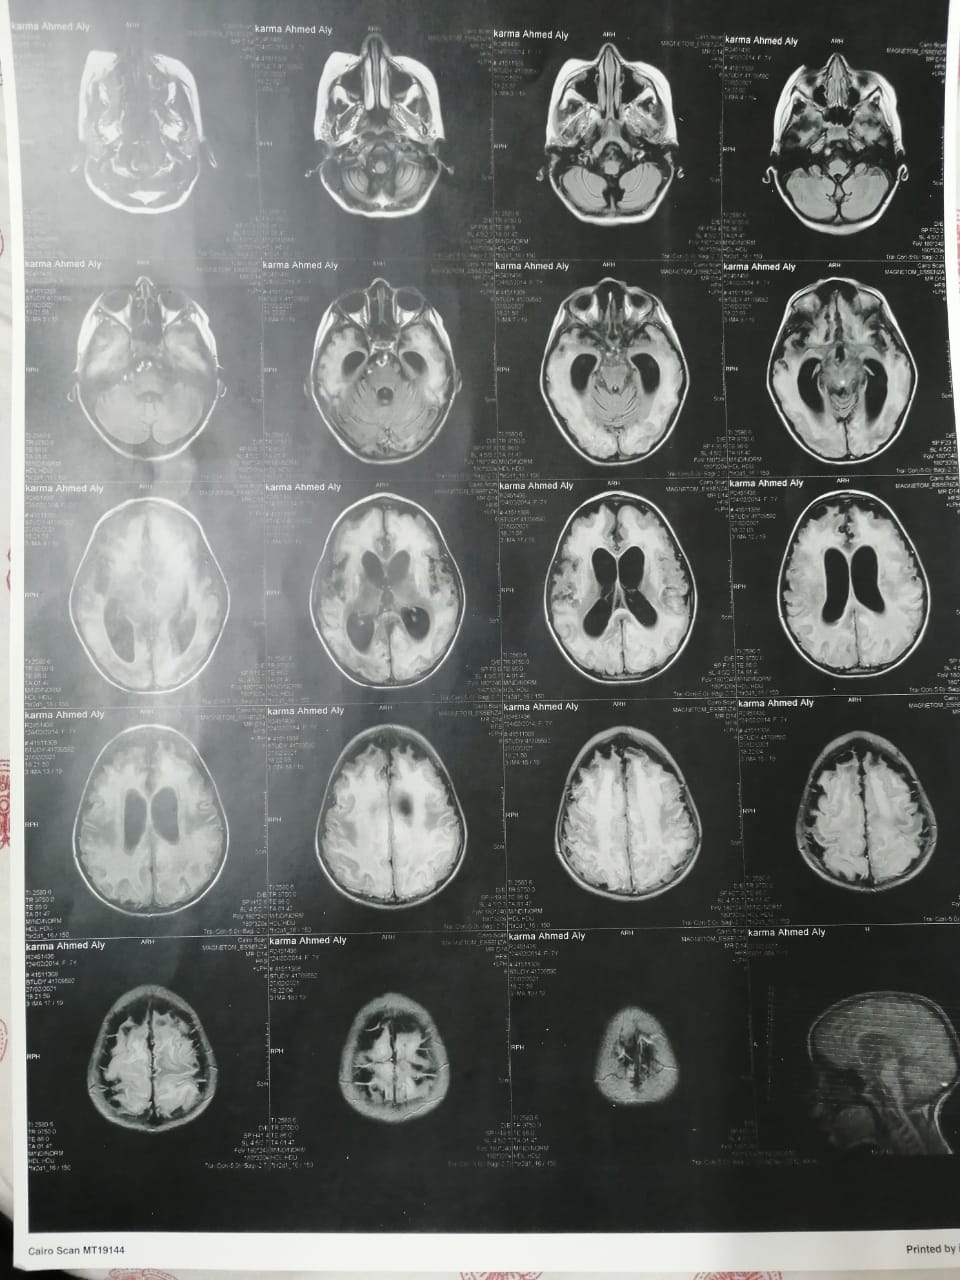

وأشار إلى أنه بعد خروج كارما من المستشفى تم إجراء فحوصات أخرى عليها، تبينت عدم التطابق بين التقارير الطبية لها بداخل المستشفى والفحوصات الجديدة.

وقال علي: "بنتي جالها ضمور في المخ وفي كل الحواس، بسبب الدوا الغلط، بنعملها علاج طبيعي بيتكلف في الشهر 20 ألف جنيه"، مشددًا": "هي بتفتح عينها بس".